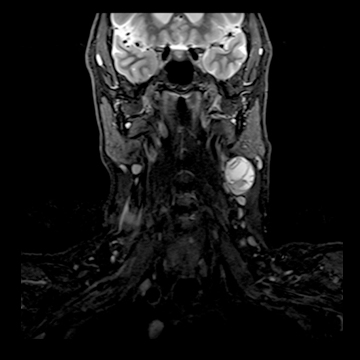

頚部腫瘍

- 造影3D VIBE

- 体動の影響を受けにくい